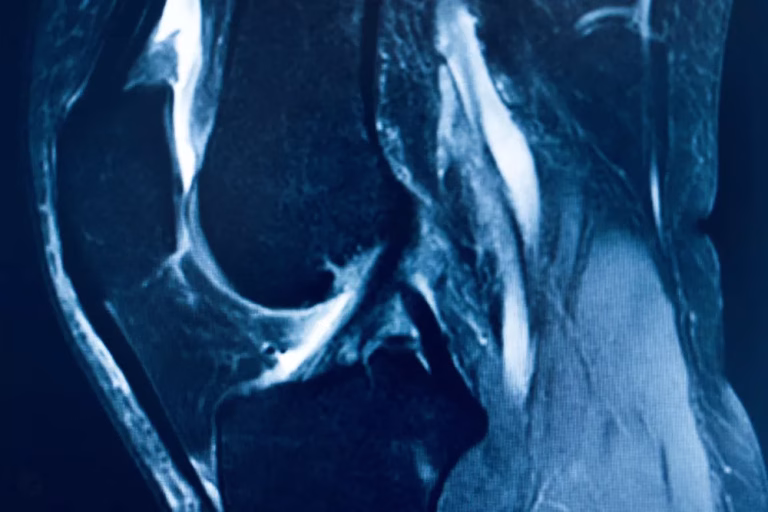

- Rezonanță magnetică (RMN): oferă imagini detaliate ale țesuturilor moi, confirmând ruptura ligamentului încrucișat anterior și identificând eventuale leziuni asociate, precum cele meniscale